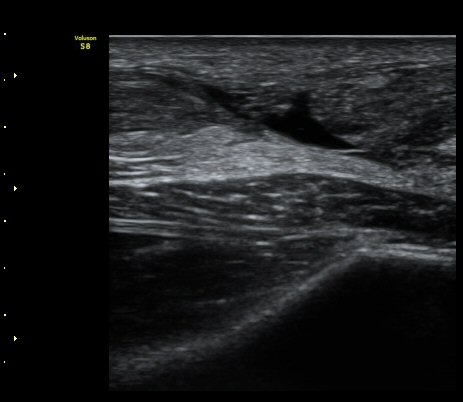

[¹ß¸ñ] ¾ÆÅ³·¹½º ÈûÁÙ ÆÄ¿­ÀÇ ÃÊÀ½ÆÄ Áø´Ü

ÁÂÃø ¹ß¸ñÀÇ ÅëÁõ(2ÁÖ)

2ÁÖ Àü ¹èµå¹ÎÅÏÇÏ´Ù°¡ ¹ß¸ñÀÇ ÅëÁõÀÌ ¹ß»ýÇÏ¿© Ÿº´¿ø¿¡¼­ ÃÊÀ½ÆÄ°Ë»ç µî ½ÃÇàÇÏ°í ºÎ¸ñ°íÁ¤ ÈÄ ¹°¸®Ä¡·á À§ÇØ ³»¿ø

¾ÆÅ³·¹½º°Ç ºÎÁ¾ ¹× ¾ÐÅë, ´Éµ¿Àû ¹ß¸ñ ¹ß¹Ù´ÚÃø ±¼°ñ G 1, thomson test(+).

ÃÊÀ½ÆÄ °Ë»ç